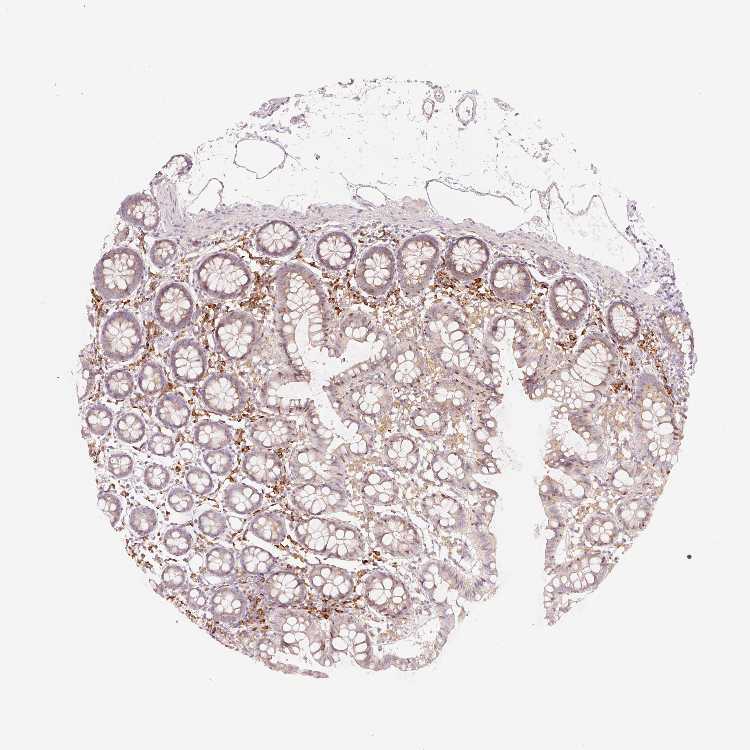

OR13C3